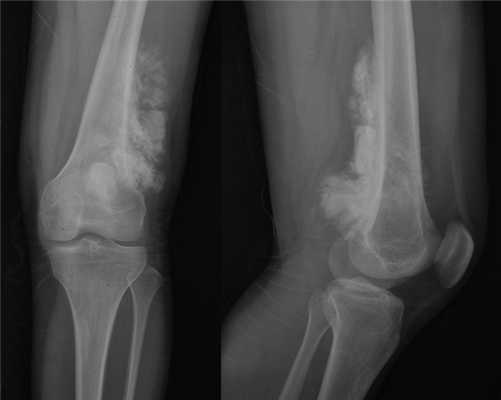

На рентгеновских снимках эозинофильная гранулема имеет вид литического очага округлой или овальной формы с четкими границами, расположенного преимущественно в костномозговой полости. При этом его размеры могут варьироваться в широких пределах. Как правило, признаки перифокального склероза отсутствуют. При поражении губчатой кости наблюдается так называемый пробойниковый дефект, а при локализации в позвоночнике может наблюдаться клиновидная деформация или формирование плоского позвонка. Таким образом, рентгенологическая картина при эозинофильной гранулеме не имеет специфических черт и во многом схожа с саркомой Юинга, остеогенной саркомой и другими злокачественными образованиями.

- Рентгенография костей. При рентгенологическом исследовании определяются единичные или множественные опухолевидные образования, участки деструкции, которые могут располагаться как в трубчатых, так и в плоских костях. При подозрении на эозинофильную гранулему обязательно проводят рентгенографию челюстей.